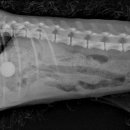

궁금하시다면⬇️ 제주 연동 호호동물병원에서 강아지 두마리 건강검진 받고 온 후기 안녕하세요! 개둘맘 세상의 희망입니다. ☺️ 오늘은 제주시 연동에 위치한 “호호동물병원”에서 강아지 ... m.blog.naver.com 제주 동물병원 추천 호호동물병원 13살 강아지 심장초음파 검사받은 후기 안녕하세요! 제주 사는 개둘맘 세상...

병원들은 대략 150 ~ 200 전후로 형성된 듯했다. 그래서 선택한 곳이 가장 가깝고 건물도 깨끗하고, 최근 개원하고, 블로그, 인스타그램도 활동하는 '제주온동물병원' 주차는 태홍누리안 5차 건물 뒤편에 지상주차장이 있는데 그곳에 주차하시면 되는데 나는 가까워서 그냥 걸어갔다. 태홍누리안 5차 그리고 동물병원...

검진 후기를 써보려고 한다!! 평소에는 강아지가 특별히 아프지 않으면 병원을 자주 가게 되진 않는다 근데 강아지 키우는 다른친구가 건강검진은 미리 받아...동물병원 브이동물병원으로 우리 멍뭉이도 건강검진 받고옴! 브이동물병원은 한라수목원 근처에 있어서 찾아가기 어렵지 않았다. 노형동 쪽에서 차로 이동...